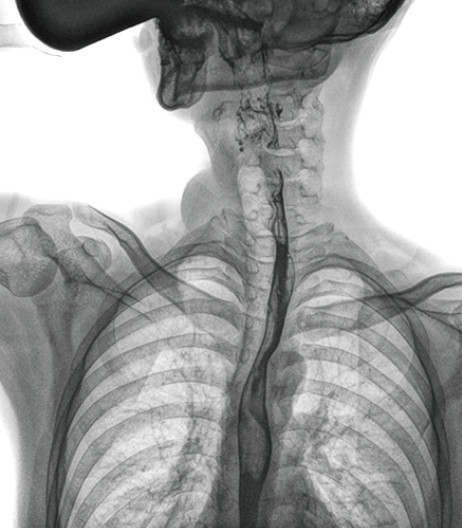

食管造影是食管病變的基本檢查方法,可以發(fā)現(xiàn)食管癌的特征性改變——食管粘膜的中斷和破壞,病人常感覺(jué)吞咽障礙,此特征在臨床中最常見,也是早期食管癌的典型表現(xiàn)。一般伴隨的特征有管壁充盈缺損、龕影、軟組織塊影、食管腔狹窄等;在透視下還可看到食管壁僵硬、蠕動(dòng)緩慢等。

動(dòng)態(tài)DR能夠?qū)崿F(xiàn)大幅面透視,瞬時(shí)高清點(diǎn)片等。在食管造影檢查中,由于吞咽鋇劑后,造影劑流速非常快,在一個(gè)大幅面上方便觀察食管的病變。瞬時(shí)點(diǎn)片,可以實(shí)時(shí)捕捉到病變部位的影像,從而可以快速做出診斷。普利德多功能動(dòng)態(tài)DR擁有17×17英寸超大視野,一次曝光即可顯示整個(gè)食管,更方便觀察食管的病變,確定病變的范圍,對(duì)診斷和治療有重要參考價(jià)值。

與過(guò)去的數(shù)字胃腸機(jī)比較,動(dòng)態(tài)DR圖像分辨率高,對(duì)食管的全景觀察,局部粘膜破壞、中斷,管腔狹窄以及病灶范圍的顯示清晰度明顯更優(yōu)。

上消化道造影高清圖像

由此不難看出,動(dòng)態(tài)DR在食管造影的臨床應(yīng)用上,相比于其他檢查手段,成像清晰、應(yīng)用便捷,而且能夠充分顯示食管的局部和整體結(jié)構(gòu)形態(tài),并以此揭示相關(guān)形態(tài)和功能性改變,更有利于助力實(shí)現(xiàn)精準(zhǔn)診斷。